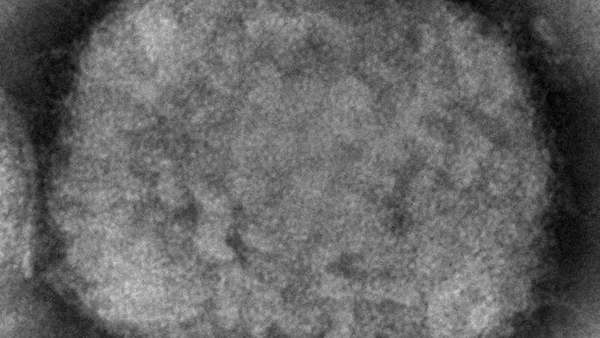

وجدري القردة مرض نادر وعادة ما تكون أعراضه الحمى وآلام العضلات وتضخم الغدد اللمفاوية وطفح جلدي على اليدين والوجه.